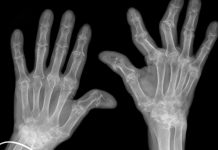

Meno nominata dell’artrosi che colpisce anca, ginocchio e spalla, l’artrosi dell’articolazione trapezio-metacarpale è tra le più diffuse nella popolazione generale, con un’incidenza del 20% su scala mondiale. Si tratta di una patologia che colpisce con prevalenza maggiore le donne nel post-menopausa, con una incidenza del 30%, e che procura dolore nei movimenti di forza che richiedono l’azione del pollice e, nel tempo, anche in quelli fini.

Un recente studio giapponese valuta la correlazione esistente tra instabilità articolare in pazienti colpiti da artrosi trapezio-metacarpale, o rizoartrosi, ed equilibrio tra i primi muscoli interossei dorsali e i muscoli oppositori del pollice durante la presa a pinza di un oggetto. L’ipotesi è che una perdita di equilibrio tra questi gruppi muscolari possa determinare una maggiore instabilità a carico dell’articolazione trapezio-metacarpale, già acuita nei pazienti con artrosi. Lo studio è pubblicato sul volume europeo di “Journal of Hand Surgery”.